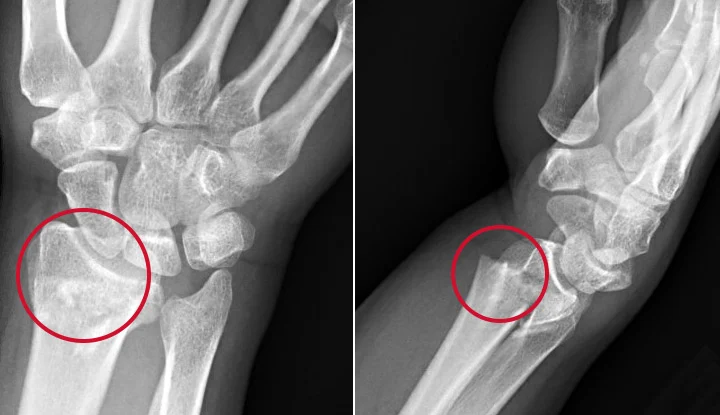

Radiological features of colles fracture: The five commonly seen deformities are:

1. Dorsal angulation with loss of the normal (5-10 degrees) volar tilt of the articular surface of the radius.

2. Dorsal displacement of the distal fracture fragment.

3. Impaction at the fracture site.

4. Radial displacement of the distal fragment.

5. Radial tilt of the distal fragment.